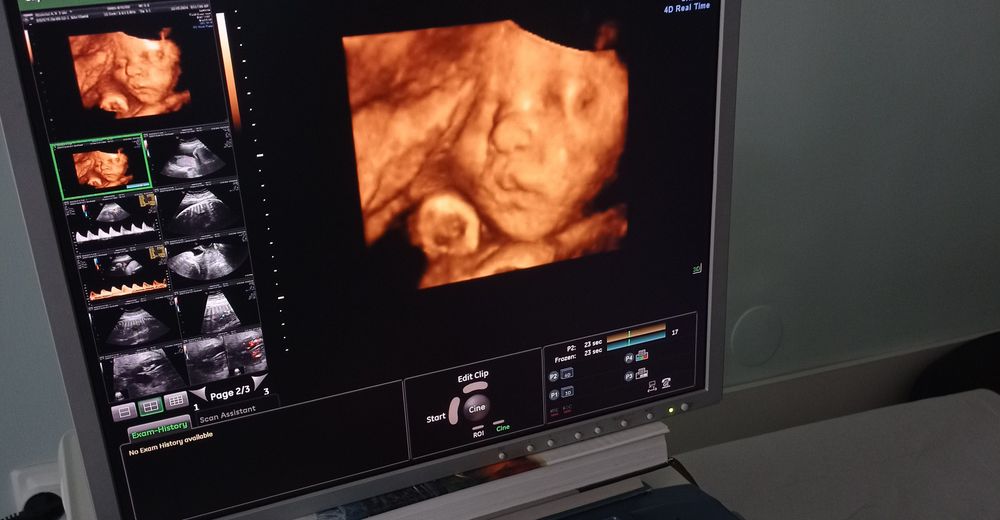

Бублик чувствует себя хорошо. Уже 1951г, все как и должно быть) Были на 3 скрининге. Улёгся вниз головой, надеюсь так и останется) Зато теперь стало ясно, чем он мне ребро подпирает, когда сижу) Был очень спокойный, готовился к фотосессии. Фотографий получилось ооочень много. Целая лента теперь есть. Можно и альбом заполняться. И все однозначно сказали, что это мамин сын. Носик мой, глаза мои большие и губки бантиком тоже. Муж пытается найти хоть что-то своё, соглашаюсь с ним) Может родится блондином, тогда это от папы) Волосы, кстати, уже 1 см у него, представляете?